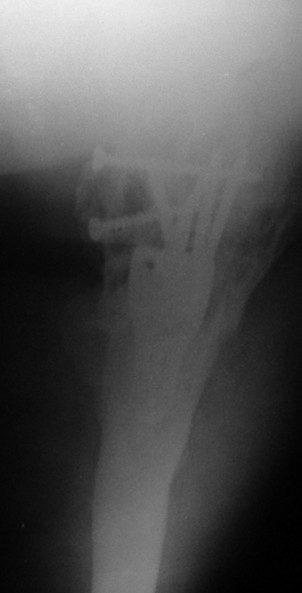

Уважаемые коллеги, каково ваше мнение по поводу необходимости удаления металлоконструкций в данном случае - мужчина, 53 лет, сопутстувующая патология - схараный диабет 2 типа, впервые выявленный, ГБ 1-2 ст., хр.калькулезный холецистит, хр.гепатит. Операция произведена в январе 2009 г. через 18 сут. после получения травмы.